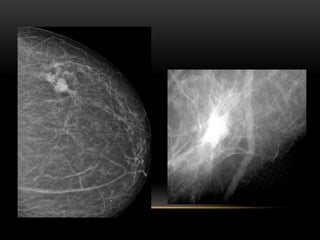

BIRADS 5

• Semiología:

• Nódulo irregular y/o márgenes espiculados, con o sin microcalcificaciones asociadas

• Microcalcificaciones lineales ramificadas

• Recomendaciones y manejo diagnóstico:

• Estudio histológico en todos los casos BAG/BAV

Probabilidad de carcinoma: Mayor de 95%